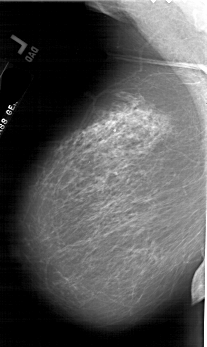

A_1773_1.LEFT_MLO

LEFT_MLO LINES 6586 PIXELS_PER_LINE 3916 BITS_PER_PIXEL 12 RESOLUTION 43.5 NON_OVERLAY